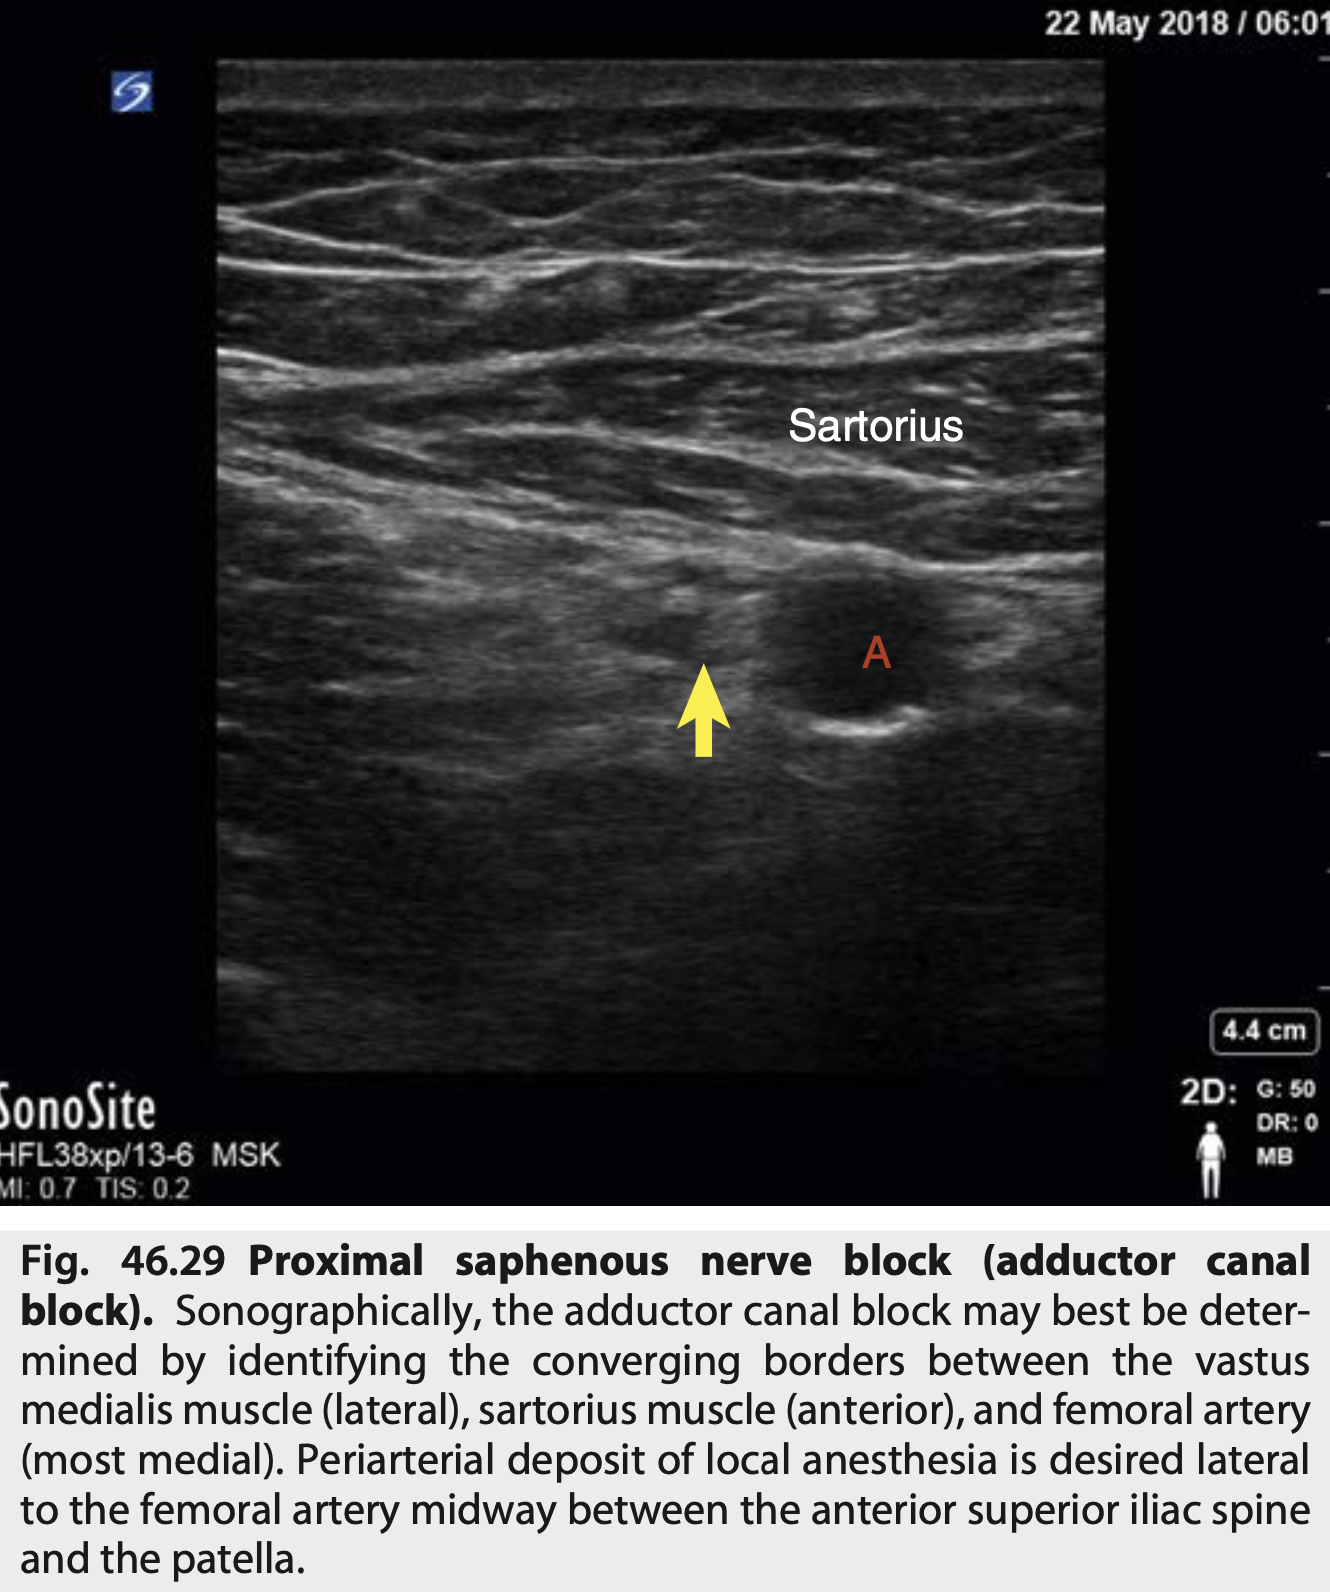

Onde deve ser colocado o AL no bloqueio de n. Safeno?

Periarterial deposit of local anesthesia is desired lateral to the femoral artery midway between the anterior superior iliac spine and the patella.

Qual o bloqueio conforme a figura?

Nervo Safeno * Ramo terminal exclusivamente sensitivo

Identificar as estruturas conforme a imagem do bloqueio Safeno

* vasto medial e lateral é bem parecido * O nervo esta antero-lateral * Atencao que o Vasto MEDIAL esta Antero-LATERAL * O Adutor Magno é o mais póstero-medial * 10ml de Anestesico local - se mais, pode subir e pegar fibras motoras do femoral